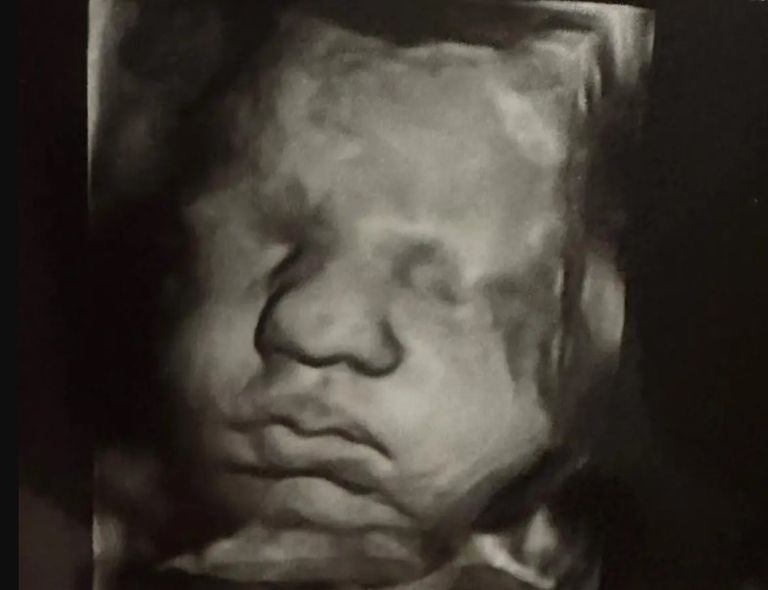

وأضافت هاتشر، خلال سردها قصتها عبر حسابها على إنستغرام، أنها خلال فحص روتيني بالموجات فوق الصوتية في مايو/ أيار 2023، علمت أنها حامل بتوأم، وأن كل جنين منهما ينمو في أحد رحميها، معلقة: "لقد أصبنا بالذهول".